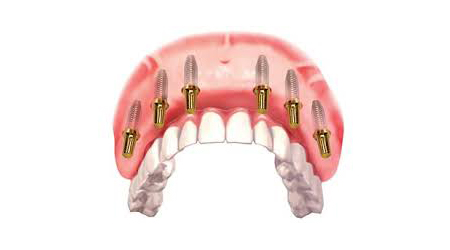

Full Mouth Rehabilitation with 6-8 Implants Protocol for good bone

Upper Jaw/Lower Jaw (Per Jaw)- NOBEL BIOCARE

Technique INR US

6-8 NOBLE BIOCARE Implants + 12 to 14 Units Metal Ceramic Bridge (Porcelain Fused to Metal 350000 5400

6-8 NOBLE BIOCARE Implants + 12 to 14 Units ZIRCONIUM (Metal Free) CERAMIC BRIDGE 500000 7600

Upper Jaw/Lower Jaw (Per Jaw)- ADIN

6-8 ADIN Implants + 12 to 14 Units Metal Ceramic Bridge (Porcelain Fused to Metal) 250000 3800